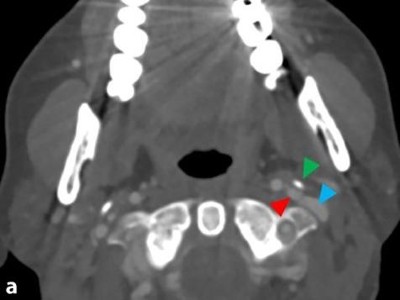

Pulsierende Ohrgeräusche nach Weihnachten – lag es wirklich am Stress?

Eine 48-jährige Patientin leidet seit Weihnachten an pulsierenden, immer lauter werdenden Ohrgeräuschen auf der linken Seite. Eine hohe Stressbelastung kommt zuerst in Frage. Doch schon der erste MRT Befund liefert einen Hinweis auf eine schwerwiegendere, organische Ursache. Hätten Sie das gesehen?

Bildnachweise